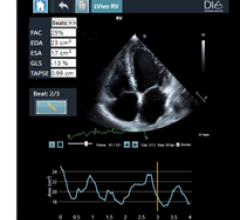

September 30, 2020 — Siemens Healthineers has introduced a new version of its c.cam dedicated cardiac nuclear medicine ...